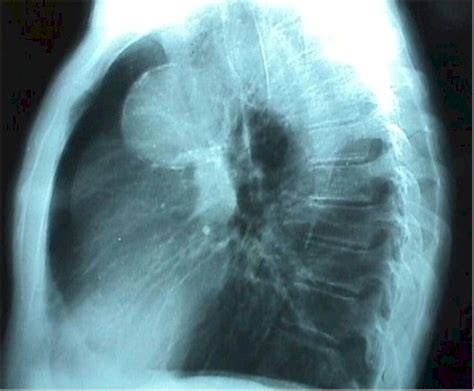

Rotura de aneurisma gigante de aorta abdominal | Medicina ...

Rotura de aneurisma gigante de aorta abdominal | Medicina ... from multimedia.elsevier.es